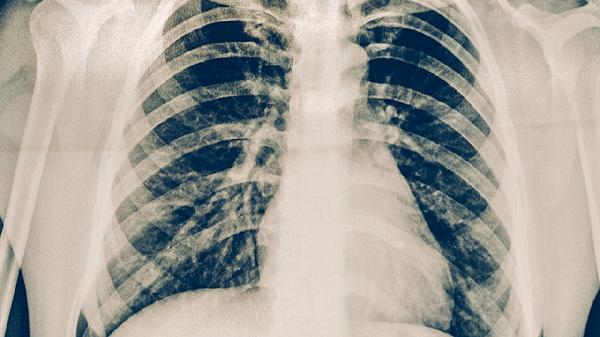

胸部X线检查能发现肺部典型结核病灶,如上叶尖后段或下叶背段的浸润性阴影、空洞形成等。对于痰检阴性的疑似患者具有重要辅助价值。但需注意与其他肺部疾病鉴别,如肺炎、肺癌等也可能出现类似影像学表现。必要时需结合CT检查进一步评估。